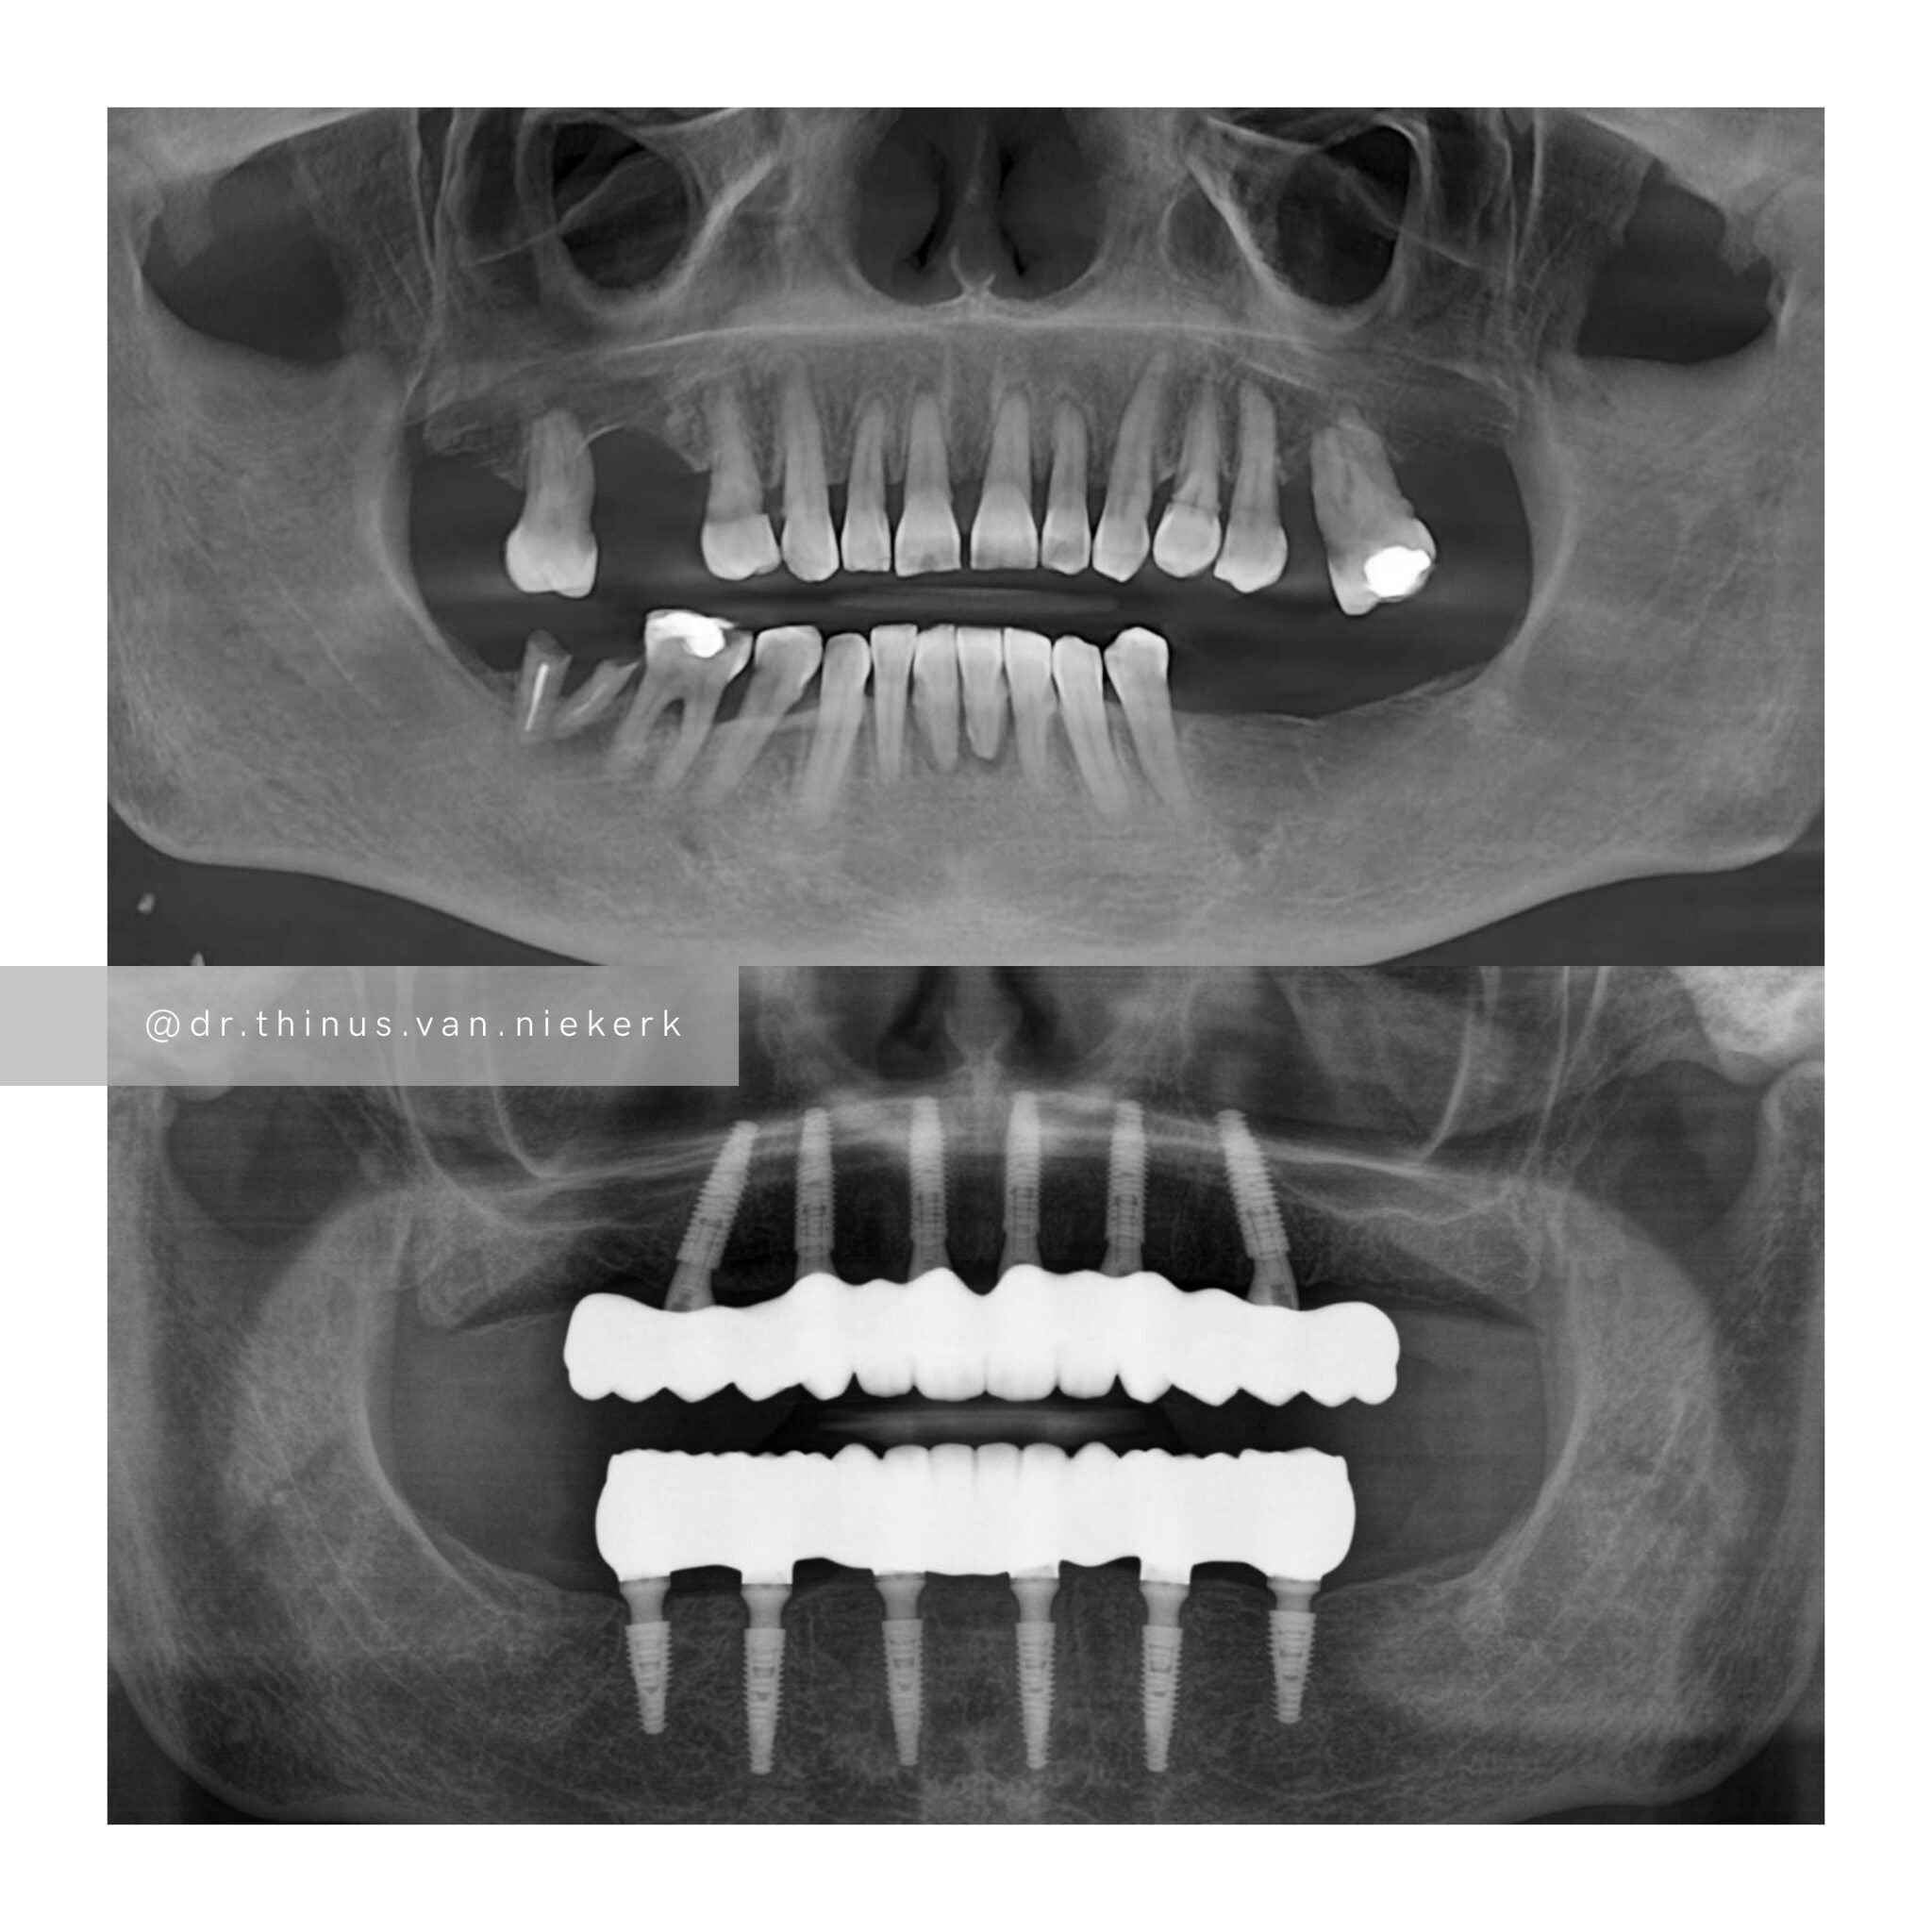

TREATMENT OBJECTIVE

Our aim was to remove all elements of infection and disease and to restore function as quickly as possible. The complete case was digitally planned prior to the day of surgery. Six fully-guided implants were placed during a two-hour morning surgery. An immediate implant-supported prosthesis was delivered on the same day.

COMMENTS

This case demonstrated the power and effectiveness of digital implant-surgery planning and CAD design software.